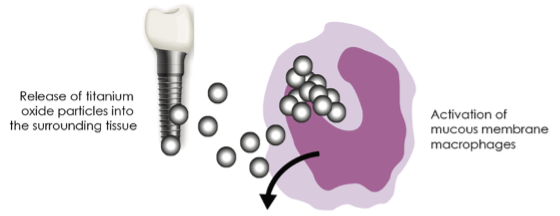

Nenhum metal ou liga é completamente inerte in vivo, podendo sofrer corrosão em maior ou menor grau e, embora as ligas de titânio sejam das mais resistentes, também sofrem corrosão libertando micropartículas e iões no organismo.

Resposta geral

Vários estudos demonstraram que os iões que se libertam de implantes metálicos, dentários e ortopédicos, além de se concentrarem em torno dos mesmos, podem ser detetados em linfonodos regionais, no tecido pulmonar, no plasma sanguíneo e até na urina. Em pessoas susceptíveis, com um sistema imunitário hiperactivo, a exposição crónica a estes metais pode causar numerosos outros sintomas, como inflamação crónica generalizada, desenvolvimento ou agravamento de respostas auto-imunes, dores articulares e musculares, comprometimento cognitivo (névoa cerebral), depressão e dores de cabeça.

Efeitos Imunológicos dos Metais

No corpo, os iões metálicos podem ligar-se firmemente às células, e proteínas do indivíduo, mascarando-as e tornando-as irreconhecíveis para o sistema imunitário*, levando a uma resposta de ataque autoimune, o que pode agravar situações autoimunes que a pessoa já tinha ou criar novas perturbações auto-imunitárias.